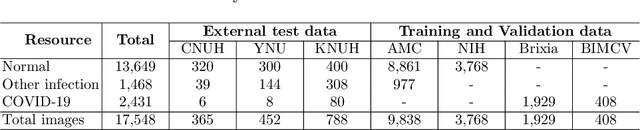

Abstract:Developing a robust algorithm to diagnose and quantify the severity of COVID-19 using Chest X-ray (CXR) requires a large number of well-curated COVID-19 datasets, which is difficult to collect under the global COVID-19 pandemic. On the other hand, CXR data with other findings are abundant. This situation is ideally suited for the Vision Transformer (ViT) architecture, where a lot of unlabeled data can be used through structural modeling by the self-attention mechanism. However, the use of existing ViT is not optimal, since feature embedding through direct patch flattening or ResNet backbone in the standard ViT is not intended for CXR. To address this problem, here we propose a novel Vision Transformer that utilizes low-level CXR feature corpus obtained from a backbone network that extracts common CXR findings. Specifically, the backbone network is first trained with large public datasets to detect common abnormal findings such as consolidation, opacity, edema, etc. Then, the embedded features from the backbone network are used as corpora for a Transformer model for the diagnosis and the severity quantification of COVID-19. We evaluate our model on various external test datasets from totally different institutions to evaluate the generalization capability. The experimental results confirm that our model can achieve the state-of-the-art performance in both diagnosis and severity quantification tasks with superior generalization capability, which are sine qua non of widespread deployment.

Abstract:Under the global COVID-19 crisis, developing robust diagnosis algorithm for COVID-19 using CXR is hampered by the lack of the well-curated COVID-19 data set, although CXR data with other disease are abundant. This situation is suitable for vision transformer architecture that can exploit the abundant unlabeled data using pre-training. However, the direct use of existing vision transformer that uses the corpus generated by the ResNet is not optimal for correct feature embedding. To mitigate this problem, we propose a novel vision Transformer by using the low-level CXR feature corpus that are obtained to extract the abnormal CXR features. Specifically, the backbone network is trained using large public datasets to obtain the abnormal features in routine diagnosis such as consolidation, glass-grass opacity (GGO), etc. Then, the embedded features from the backbone network are used as corpus for vision transformer training. We examine our model on various external test datasets acquired from totally different institutions to assess the generalization ability. Our experiments demonstrate that our method achieved the state-of-art performance and has better generalization capability, which are crucial for a widespread deployment.